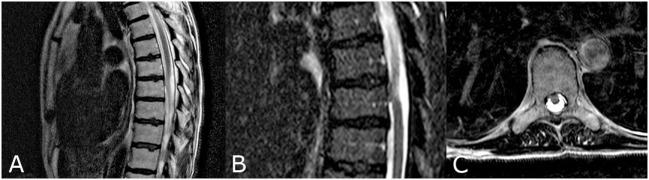

Idiopathic ventral herniation of the spinal cord (SC) is not often encountered in daily practice. Its clinical prevalence, however, will increase through increasing awareness and more frequent use of MRI. A clear explanation of its pathophysiology has never been formulated. It was hypothesized that the findings during surgery might indicate the real causative mechanism. An extensive literature search was performed, using Embase, PubMed, and Google Scholar. Titles and abstracts were screened by two investigators, using strict inclusion and exclusion criteria. Reference lists of the full paper versions of each included article were checked. The following data were registered for the articles included: age, gender, level of herniation, relation to intervertebral disk, duration of symptoms, findings from surgery, and outcomes. Nine cases treated at our department were added. A total of 117 articles reporting on 259 patients were included. Including our cases, 268 patients were reviewed. Females outnumbered males (160/100). The mean age was 51.3 ± 12.0 years. In 236 patients, the duration of symptoms was reported: 55.5 ± 55.6 months. In 178 patients, the intraoperative findings for the herniated part of the SC were not mentioned. In 59 patients, a tumor-like extrusion was seen, without any alteration to the SC. Deformation of the SC itself was never observed. Biopsies of these structures were without clinical consequence. Based on the intraoperative findings reported in literature and the cases presented, acquired causes, such as trauma and erosion of the dura due to a herniated disk, were not plausible. We hypothesize that a non-functioning appendix to the SC can only develop during an early embryologic phase, in which several layers separate. We propose renaming this entity as congenital transdural appendix of the SC.

特发性脊髓腹侧疝在日常临床实践中并不常见。然而,随着对其认识的提高以及磁共振成像(MRI)使用的增多,其临床患病率将会上升。目前尚未对其病理生理学做出明确解释。据推测,手术中的发现可能提示真正的致病机制。我们使用Embase、PubMed和谷歌学术进行了广泛的文献检索。两名研究人员依据严格的纳入和排除标准对标题和摘要进行筛选,并检查了每篇纳入文章全文版本的参考文献列表。对纳入文章记录了以下数据:年龄、性别、疝出水平、与椎间盘的关系、症状持续时间、手术发现及结果。我们科室治疗的9例病例也被纳入。总共纳入了117篇报告259例患者的文章。包括我们的病例在内,共对268例患者进行了回顾。女性多于男性(160/100)。平均年龄为51.3±12.0岁。236例患者报告了症状持续时间:55.5±55.6个月。178例患者未提及脊髓疝出部分的术中发现。59例患者可见肿瘤样突出,脊髓无任何改变。从未观察到脊髓本身变形。对这些结构进行活检未产生临床后果。基于文献报道的术中发现及所呈现的病例,诸如创伤和椎间盘疝导致硬脊膜侵蚀之类的后天性病因似乎不太可能。我们推测,脊髓的无功能附属结构只能在胚胎发育早期形成,此时有几层结构分离。我们建议将此实体重新命名为先天性脊髓经硬脊膜附属结构。